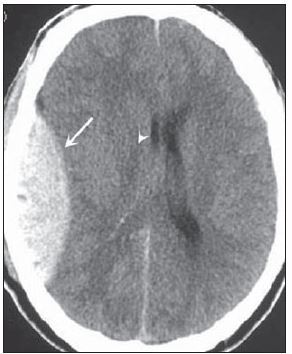

Hemorragia Subaracnóide (HSA)

O que mostra a TC?

Lesão hiperdensa (branca),

logo no início dos sintomas.

Exames diagnósticos?

TC sem contraste: “mickey”;

Arteriografia: localiza a lesão vascular.